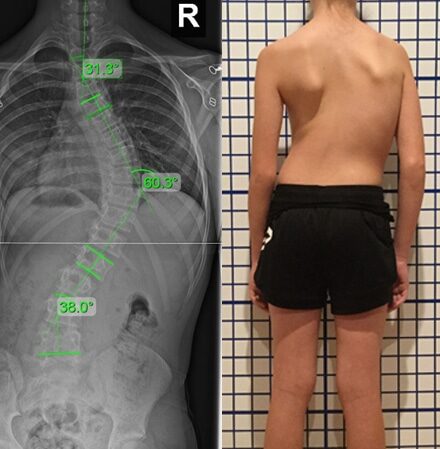

هل اعوجاج العمود الفقري يسبب ألماً عند الأطفال؟ أعرف الأعراض والعلاج المبكر يُعدّ اعوجاج العمود الفقري، أو ما يُعرف بالجنف، من المشكلات الشائعة بين الأطفال والمراهقين. كثير من الأهل يلاحظون انحناء غير طبيعي في

أهمية علاج اعوجاج العمود الفقري مبكرا عند للأطفال | كيف تمنع الجراحة وتحمي طفلك احذر… التطور سريع، والعلاج المبكر هو الحل هل سمعت من قبل نصيحة تقول: “لننتظر ونرى” عندما شككت بوجود اعوجاج في

الفحص المبكر لاعوجاج العمود الفقري: سر تجنب الجراحة وخفض التكاليف للأطفال والمراهقين اعوجاج العمود الفقري أو الجنف من المشكلات الصحية التي قد تظهر في سن مبكرة، خصوصًا عند الأطفال والمراهقين. الكثير من الأهل والمرضى